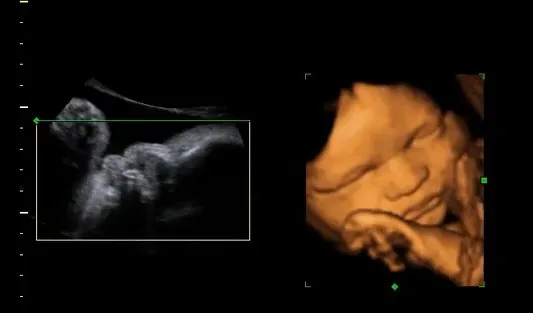

W 31. tygodniu ciąży Twoje dziecko kontynuuje swój dynamiczny wzrost. Średnio, w tym czasie maluszek waży już od 1500 do 1800 gramów, a jego długość, mierzona od czubka głowy do stóp, wynosi około 41-42 centymetrów. Aby łatwiej sobie to wyobrazić, pomyśl, że Twoje dziecko jest już wielkości kokosa lub dużej główki sałaty. To naprawdę spory maluch, który wciąż ma jeszcze trochę miejsca, by rosnąć!

- Badanie USG: Lekarz może zlecić badanie USG w celu oceny wzrostu i wagi dziecka, położenia, ilości płynu owodniowego oraz przepływów krwi.